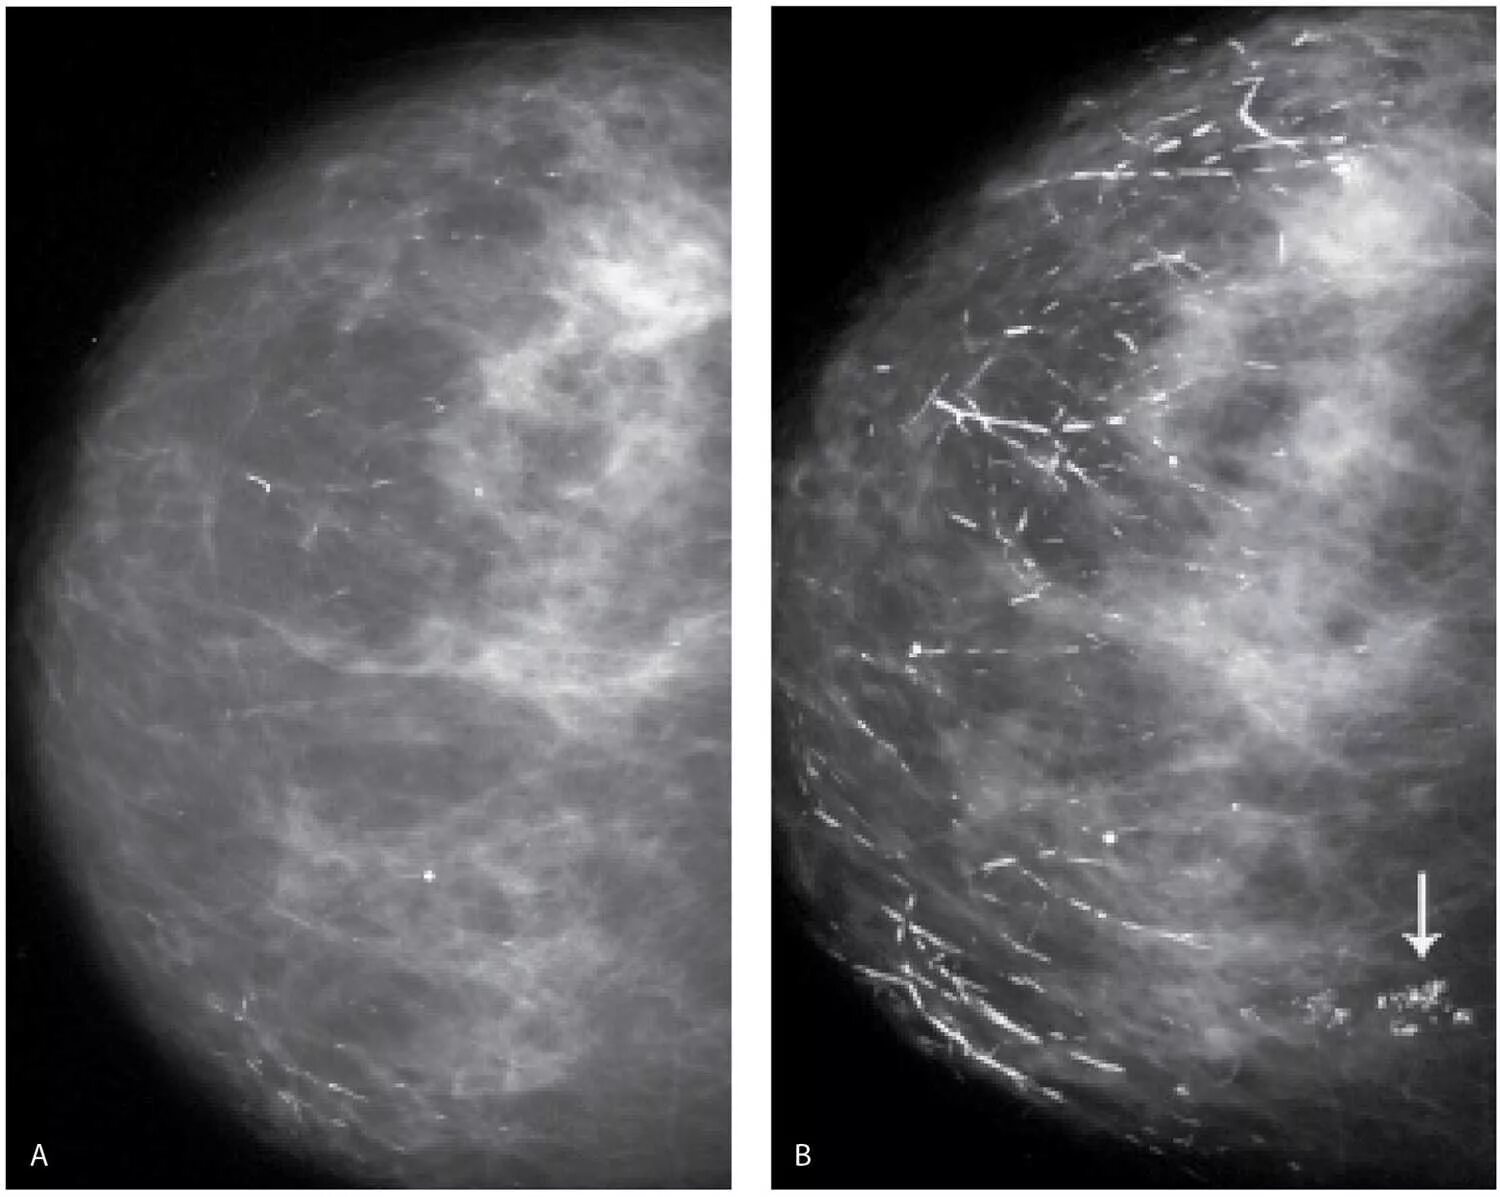

Что значит кальцинат в молочной железе